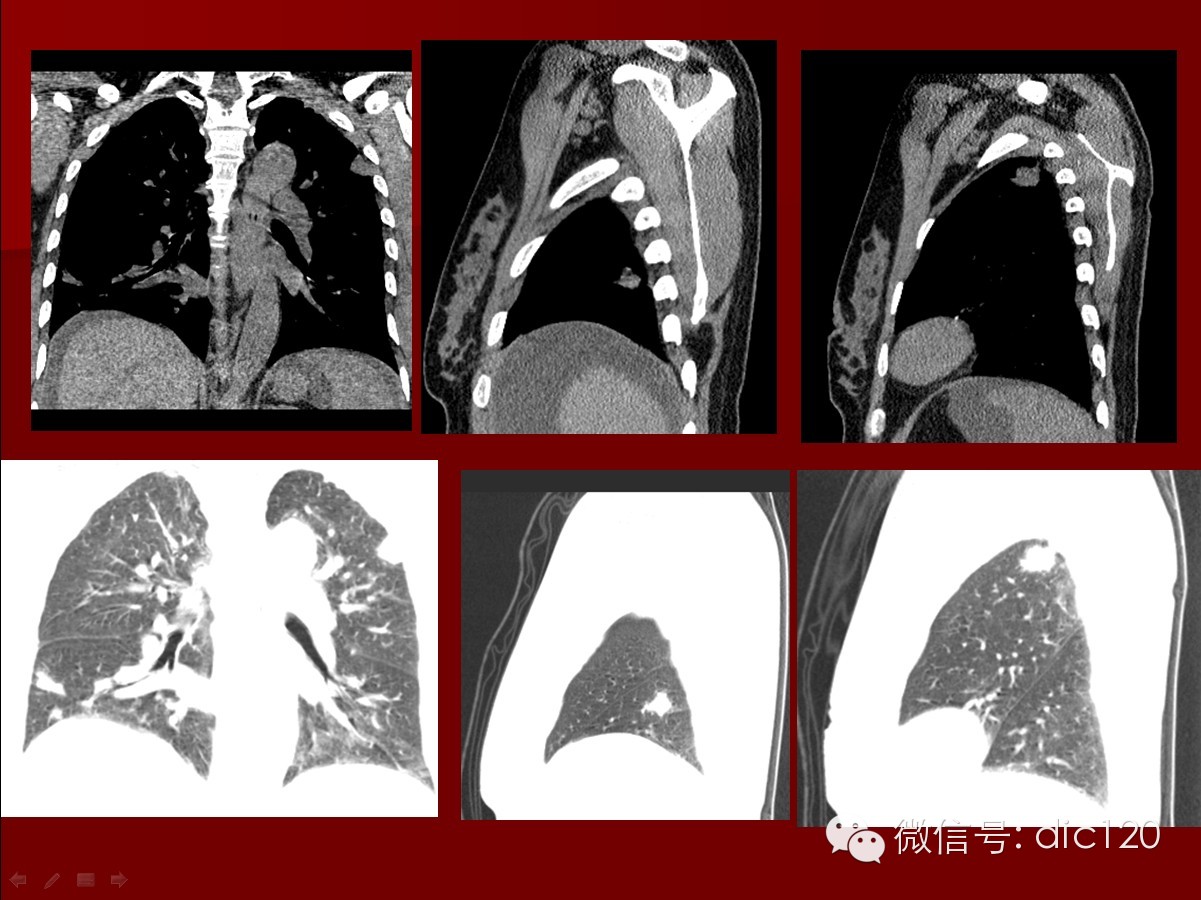

本病影像肺内表现特征:1)结节、球形肿块及空洞:病灶可单发也可多发,病灶多见于两肺下叶,也可位于肺尖,且肺外带好发,2/3病例球形肿块内出现空洞,洞壁较厚、不规则,其中可见液平,用免疫抑制剂及肾上腺皮质激素治疗,病灶可缩小或消失,病情恶化时可出现新病灶。斑片状影:较为少见,为肺血管炎引起的肺出血和肺梗死,合并炎症也可出现,病灶较大可占据一个肺段,病灶可在1~2周内缩小或消失,但又可出现新的病灶。